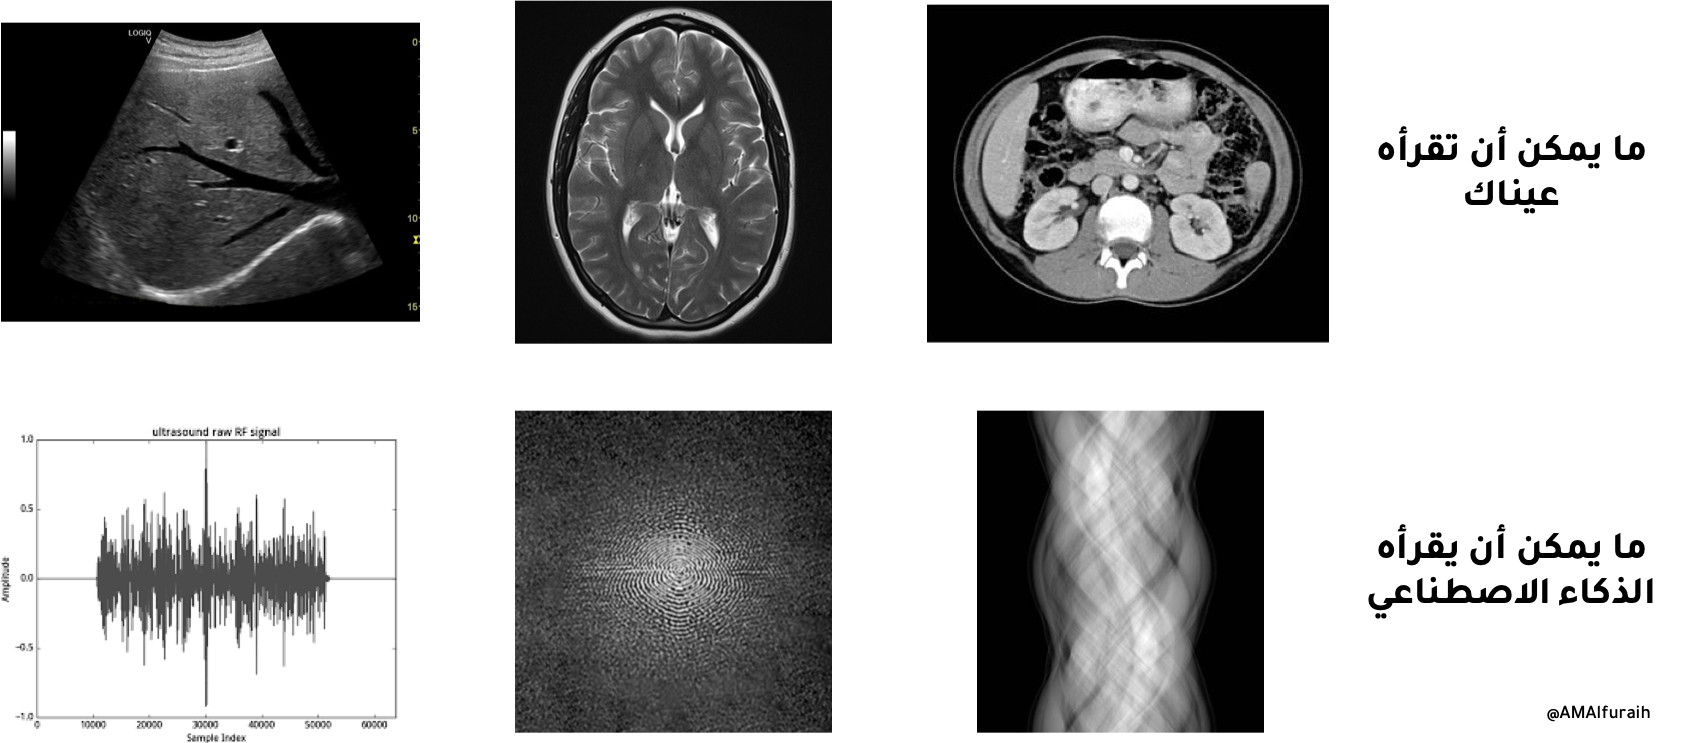

من مميزات الذكاء الاصناعي أنه لايحتاج لقراءة نفس الصور التي نراها نحن. بل بإمكانه قراءة Sinogram في الأشعة المقطعية والـ k-space في الرنين المغناطيسي وبيانات RF في الموجات فوق الصوتية.